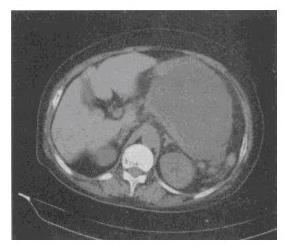

患者,男性,32岁。突发上腹痛1个月,疼痛剧烈伴发热,血清淀粉酶升高。CT检查见附图,最可能的诊断是()。

A、胰腺浆液性囊腺瘤

B、胰岛细胞瘤

C、急性胰腺炎并假囊肿形成

D、胰腺癌

E、小肠肿瘤

C